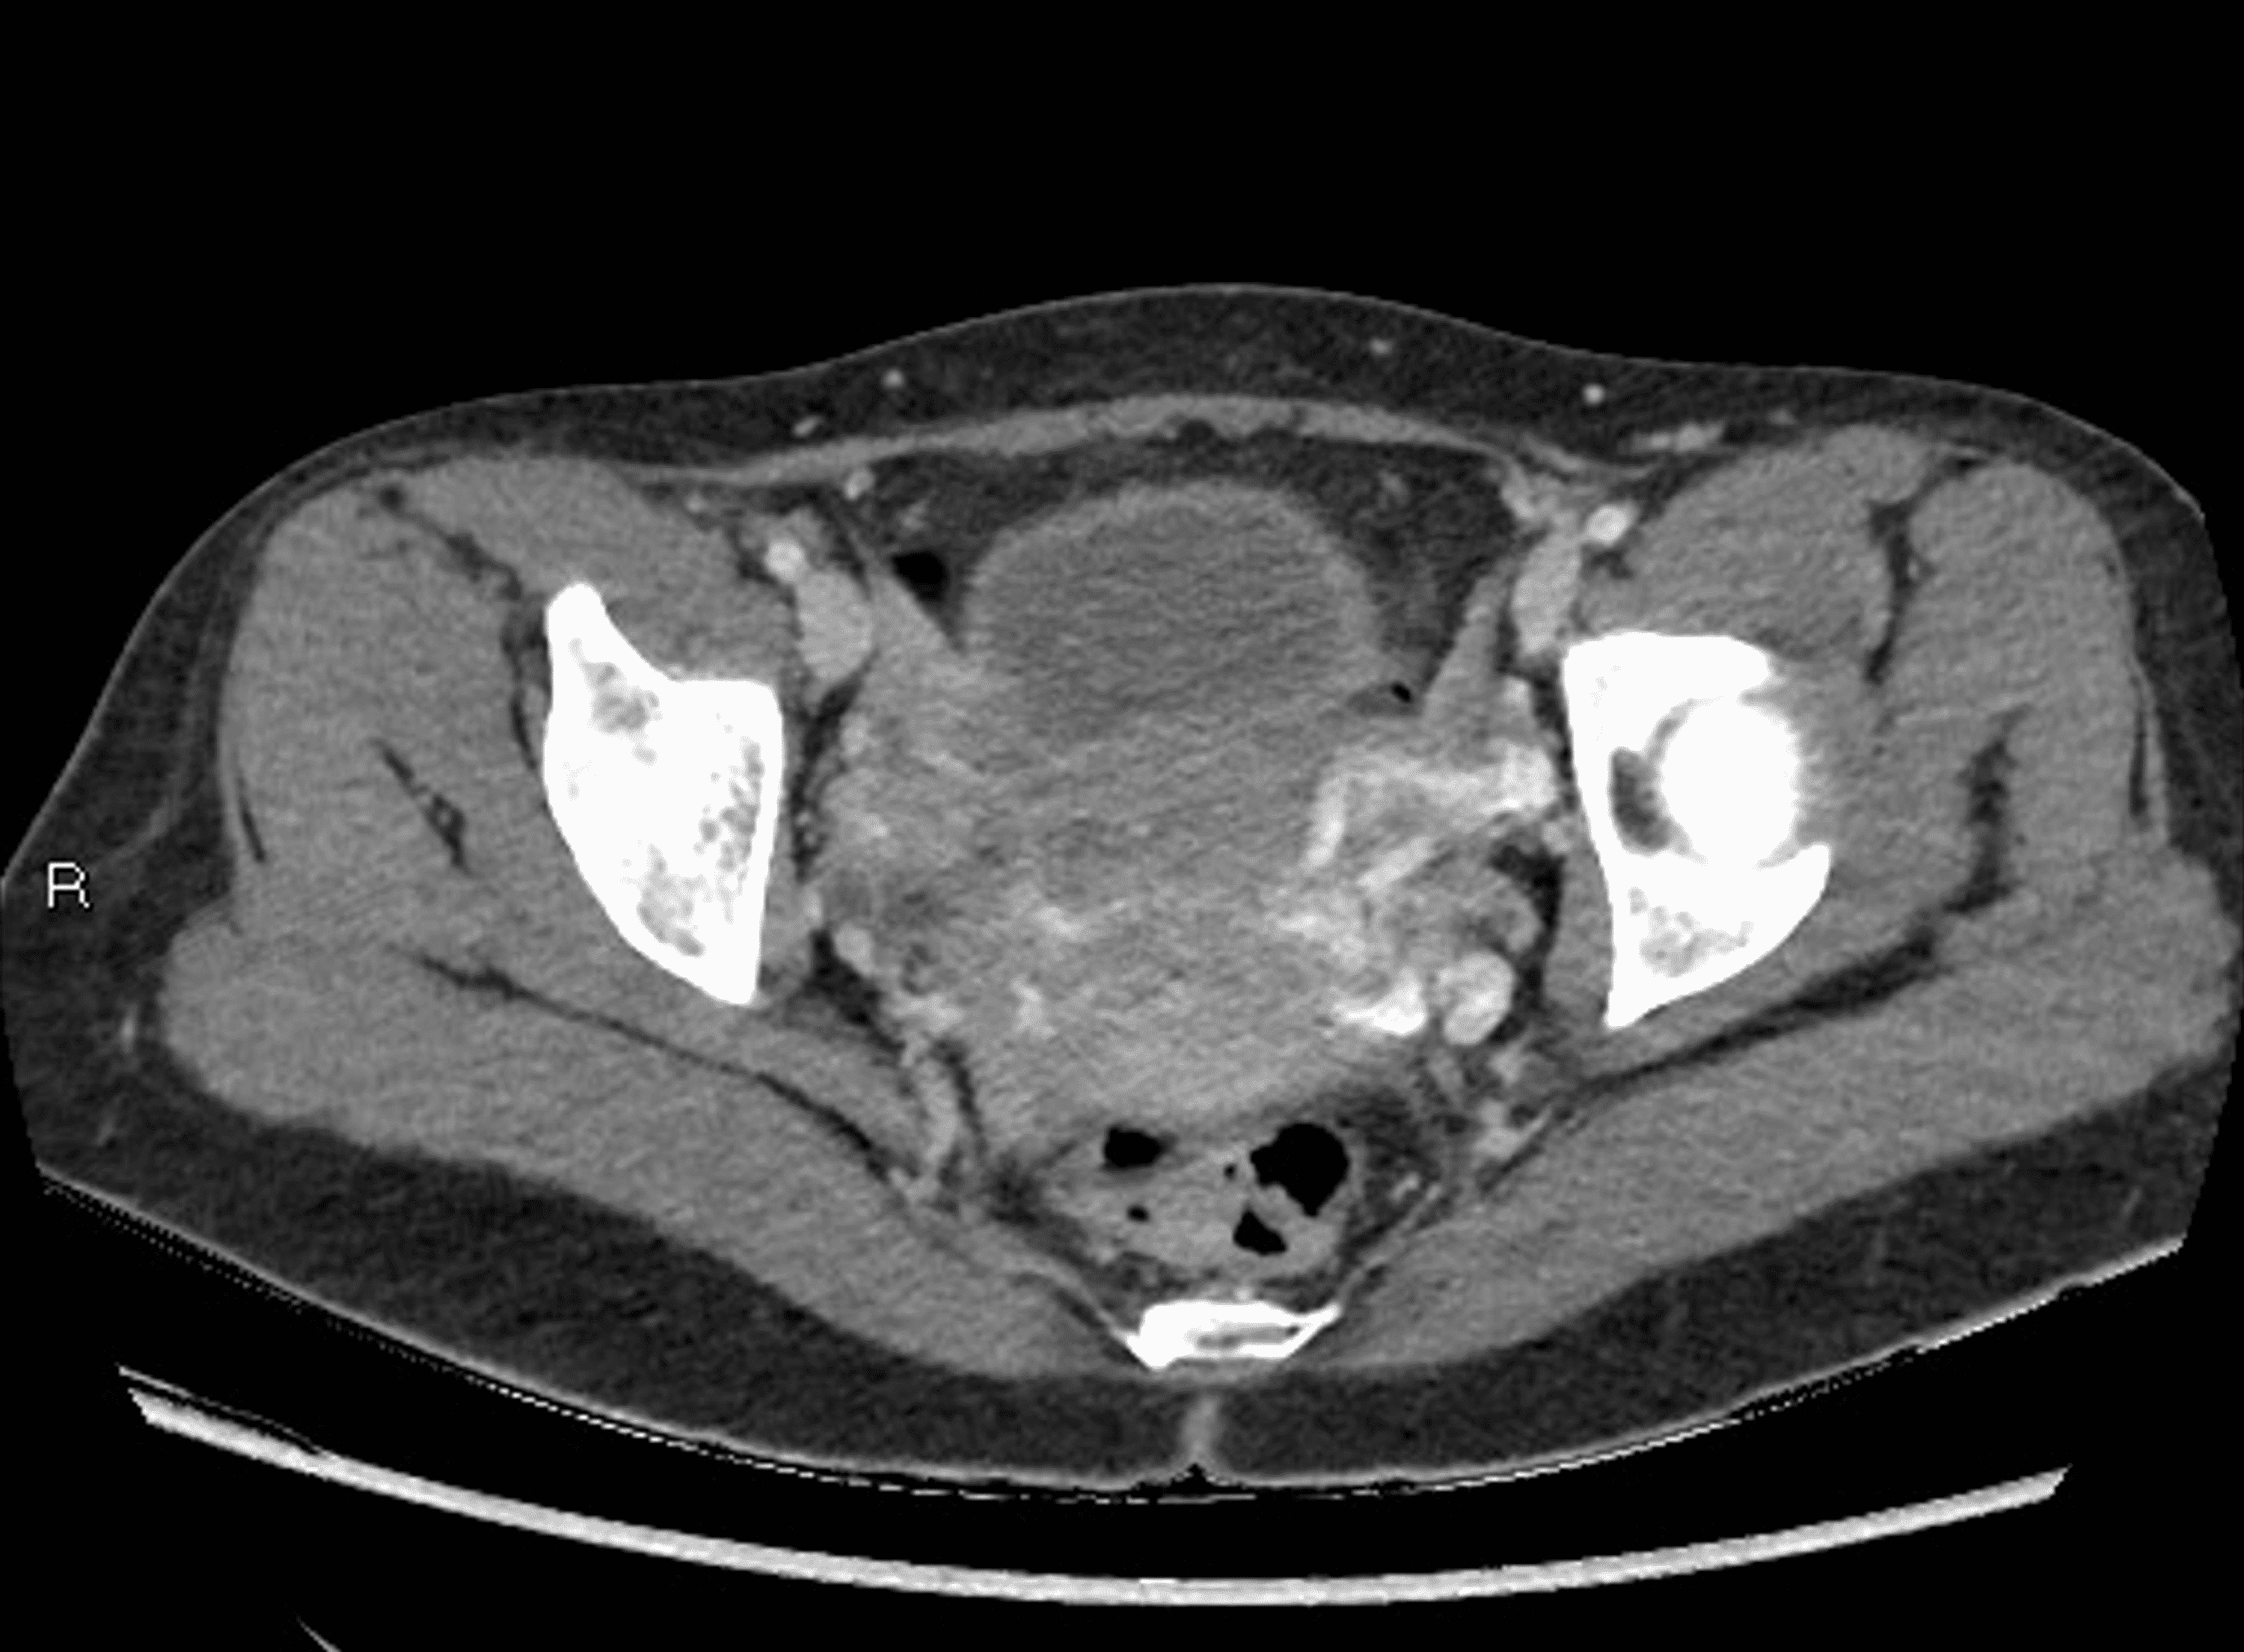

From www.cureus.com

Cureus An Unusual Cause of Abdominal Pain in a MiddleAged Female The Nutcracker Syndrome Nutcracker Syndrome Pain It occurs when arteries, most often the abdomen’s aorta and superior mesenteric artery,. Nutcracker syndrome (ns) is a condition in which the left renal vein becomes compressed. The nutcracker syndrome is a rare and often unrecognized cause of chronic pelvic pain and left back pain. Nutcracker syndrome is the clinical manifestation of the nutcracker phenomenon. Often, patients have had several. Nutcracker Syndrome Pain.

Cureus An Unusual Cause of Abdominal Pain in a MiddleAged Female The Nutcracker Syndrome Nutcracker Syndrome Pain Nutcracker syndrome is the clinical manifestation of the nutcracker phenomenon. This can restrict blood flow, which may lead to symptoms such as left flank pain and blood and protein. Patients most commonly present with unexplained hematuria and flank or pelvic pain, which can be severe at times. These symptoms are due to the left. Nutcracker syndrome (ncs) is an extrinsic. Nutcracker Syndrome Pain.

An Unusual Cause of Abdominal Pain in a MiddleAged Female The Nutcracker Syndrome Cureus Nutcracker Syndrome Pain It occurs when arteries, most often the abdomen’s aorta and superior mesenteric artery,. Nutcracker syndrome is a rare vein compression disorder. Nutcracker syndrome (ns) is a condition in which the left renal vein becomes compressed. Patients most commonly present with unexplained hematuria and flank or pelvic pain, which can be severe at times. This can restrict blood flow, which may. Nutcracker Syndrome Pain.